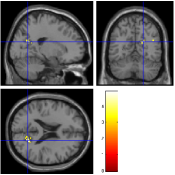

For the aC-aS contrast, Fig. 9 [top] shows, for the most significant slice and , that all pMRI reconstruction algorithms succeed in finding evoked activity in the left parietal and frontal cortices, more precisely in the inferior parietal lobule and middle frontal gyrus according to the AAL template666available in the xjView toolbox of SPM5.. Tab. 3 also confirms a bilateral activity pattern in parietal regions for . Moreover, for , Fig. 9 [bottom] illustrates that our pipeline (UWR-SENSE and 4D-UWR-SENSE) and especially the proposed 4D-UWR-SENSE scheme enables to retrieve reliable frontal activity elicited by mental calculation, which is lost by the the mSENSE algorithm. From a quantitative viewpoint, the proposed 4D-UWR-SENSE algorithm finds larger clusters whose local maxima are more significant than the ones obtained using mSENSE and UWR-SENSE, as reported in Tab. 3. Concerning the most significant cluster for , the peak positions remain stable whatever the reconstruction algorithm. However, examining their significance level, one can first measure the benefits of wavelet-based regularization when comparing UWR-SENSE with mSENSE results and then additional positive effects of temporal regularization and 3D wavelet decomposition when looking at the 4D-UWR-SENSE results. These benefits are also demonstrated for .

| mSENSE | UWR-SENSE | 4D-UWR-SENSE | |

|---|---|---|---|

|

|

|

|

|

|

|

| cluster-level | voxel-level | |||||

| p-value | Size | p-value | T-score | Position | ||

| mSENSE | 320 | 6.40 | -32 -76 45 | |||

| 163 | 5.96 | -4 -70 54 | ||||

| 121 | 6.34 | 34 -74 39 | ||||

| 94 | 6.83 | -38 4 24 | ||||

| UWR-SENSE | 407 | 6.59 | -32 -76 45 | |||

| 164 | 5.69 | -6 -70 54 | ||||

| 159 | 5.84 | 32 -70 39 | ||||

| 155 | 6.87 | -44 4 24 | ||||

| 4D-UWR-SENSE | 454 | 6.54 | -32 -76 45 | |||

| 199 | 5.43 | -6 26 21 | ||||

| 183 | 5.89 | 32 -70 39 | ||||

| 170 | 6.90 | -44 4 24 | ||||

| mSENSE | 58 | 0.028 | 5.16 | -30 -72 48 | ||

| UWR-SENSE | 94 | 0.003 | 5.91 | -32 -70 48 | ||

| 60 | 0.044 | 4.42 | -6 -72 54 | |||

| 4D-UWR-SENSE | 152 | 6.36 | -32 -70 48 | |||

| 36 | 0.009 | 5.01 | -4 -78 48 | |||

| 29 | 0.004 | 5.30 | -34 6 27 | |||

Fig. 10 illustrates another property of the proposed pMRI pipeline, i.e. its robustness to the between-subject variability. Indeed, when comparing subject-level Student’s -maps reconstructed using the different pipelines (), it can be observed that the mSENSE algorithm fails to detect any activation cluster in the expected regions for the second subject (see Fig. 10 [bottom]). By contrast, our 4D-UWR-SENSE method retrieves more coherent activity while not exactly at the same position as for the first subject.